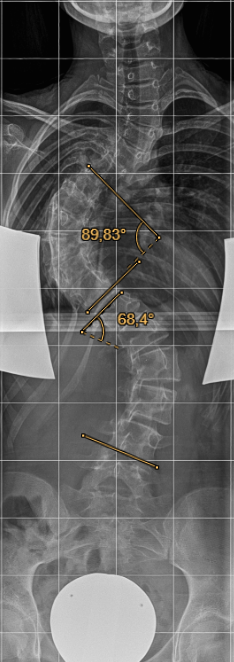

Als 13-jähriges Mädchen hatte ich natürlich große Angst vor der Operation, doch Dr. Desai und sein Team nahmen sich viel Zeit für meine Eltern und mich. Der Eingriff wurde uns ausführlich erklärt und wir hatten von Anfang an das Gefühl, in sehr kompetenten und erfahrenen Händen zu sein, was uns in unserer Entscheidung nur bestärkte. Mit einem Cobb-Winkel von fast 90 Grad im oberen Bereich und etwa 58 Grad im unteren Bereich war mir klar, dass eine Operation die einzige Möglichkeit für ein Leben ohne Korsett und ohne dauerhafte Schmerzen war.